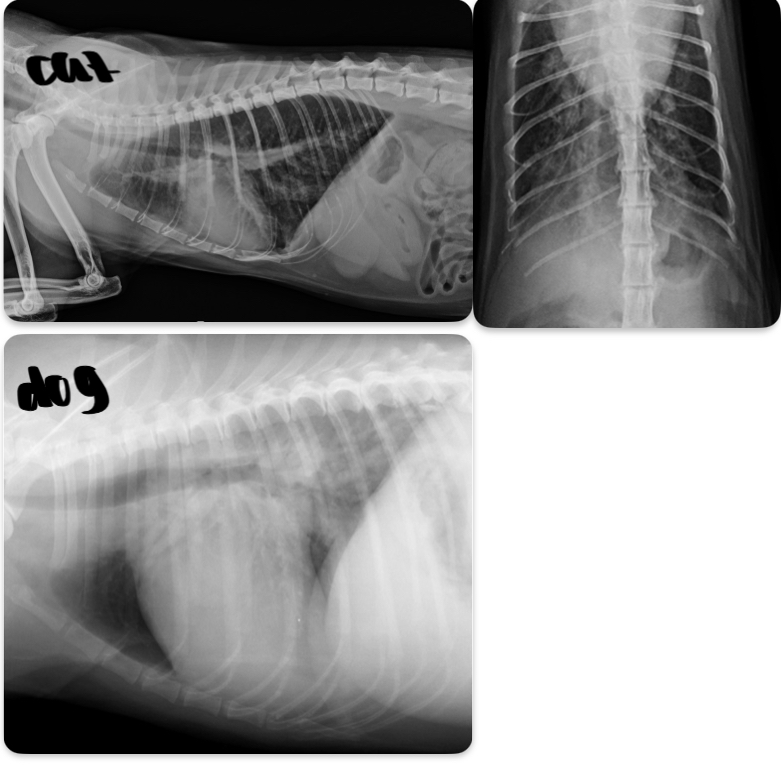

What is going on with this cat heart?

Microcardia

Cat - what sided HF is this

Dog - what sided heart failure is this

LHF